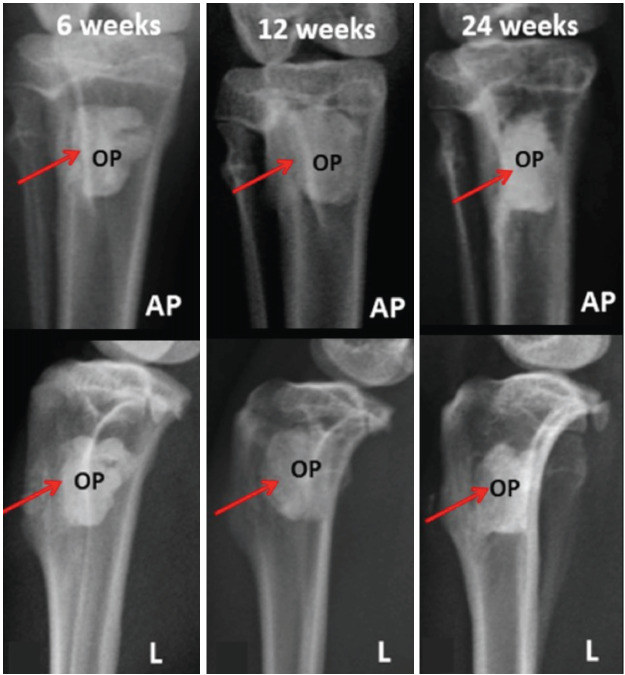

Materials and methods: A critical size defect measuring approximately 4.5mm (width) x 9.0mm (length) was surgically created at the proximal tibial metaphysis and implanted with Osteopaste, JectOS, or MIIG-X3. Following cement implantation, surrounding soft tissues were repositioned and sutured with bioabsorbable surgical suture. Bone defect healing and cement density were qualitatively and quantitatively evaluated using plain radiographs and computed tomography (CT) scans at 6, 12, and 24 weeks.

Results: The Osteopaste group showed radiographic density levels between those of JectOS and MIIG-X3. JectOS had the highest density, while Osteopaste was higher than MIIG-X3. In the Osteopaste group, new bone formation bridged the critical size defect by 12 weeks, but no bridging occurred in the other two groups at any time point. Statistical analysis showed significant differences in mean density among the groups at 6, 12, and 24 weeks (P<0.0001).